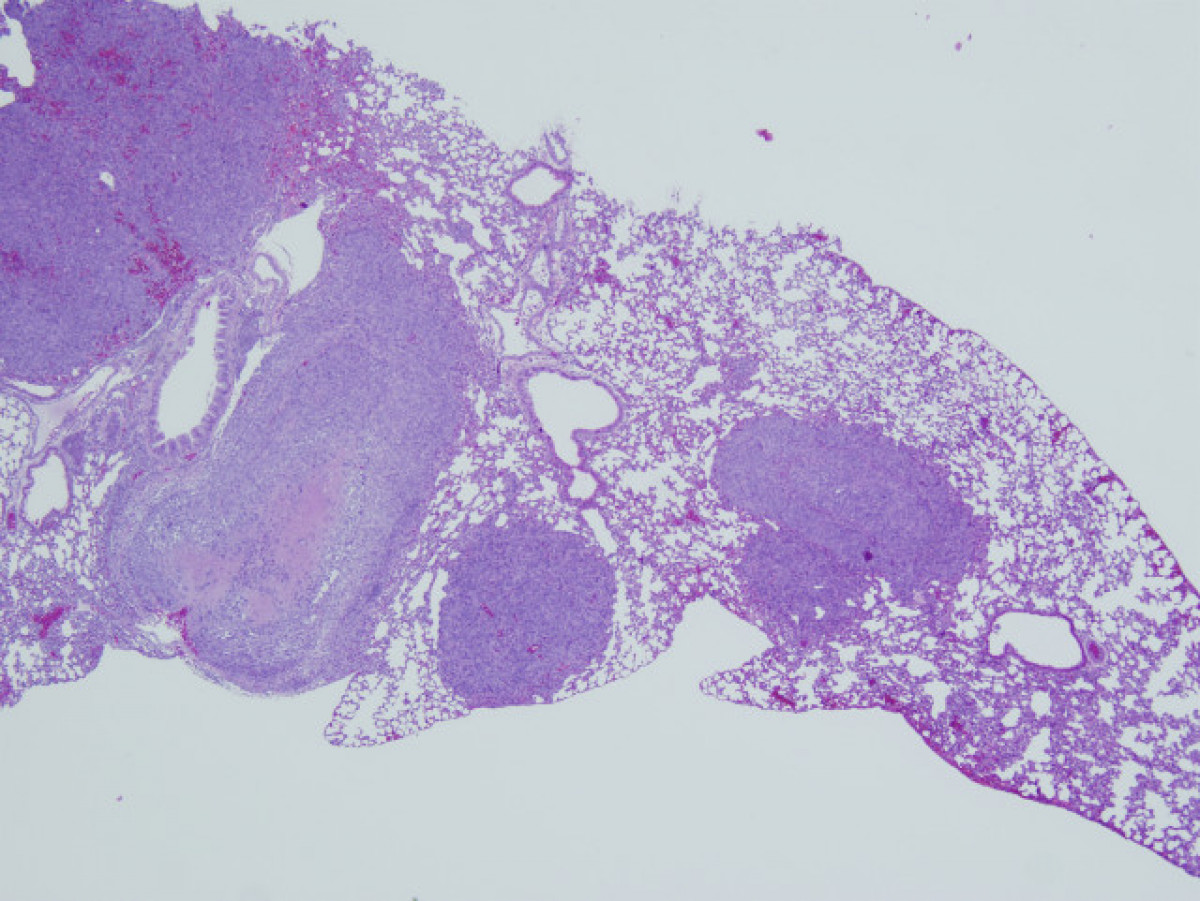

Metàstasis de pulmó @ep

Les anàlisis realitzades en el marc d'aquest estudi demostren que aquells pacients que no aconsegueixen reduir dràsticament el nombre de cèl·lules tumorals circulants després de la intervenció quirúrgica pateixen una major mortalitat, fonamentalment a conseqüència de metàstasi extrahepàtiques de l'hepatocarcinoma.